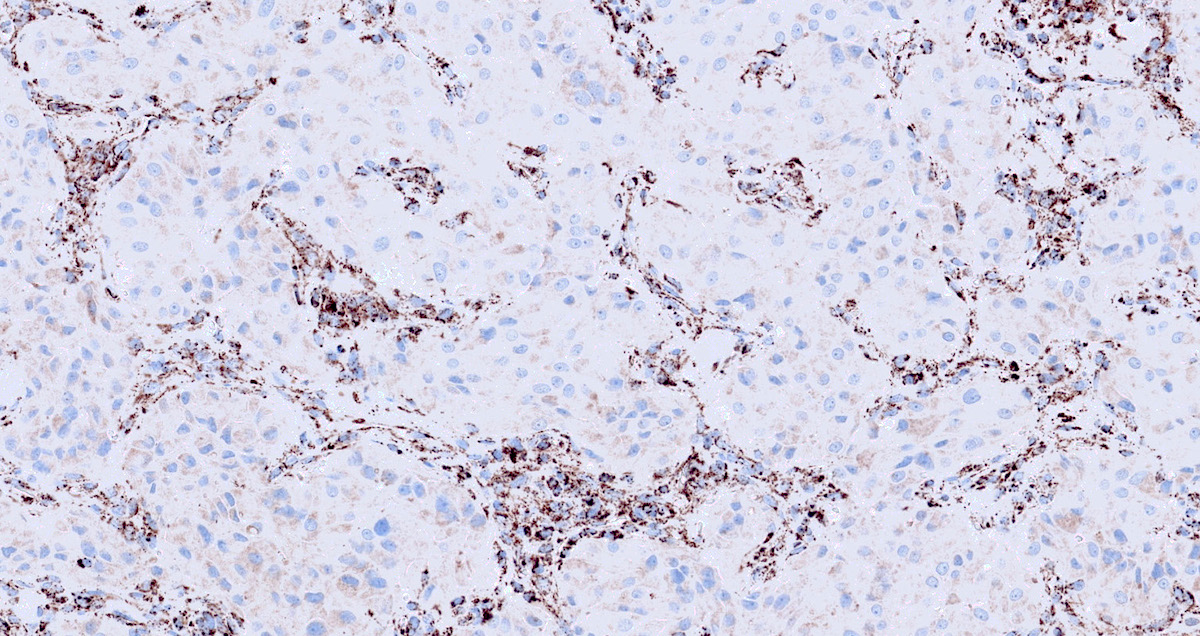

Microscopic (histologic) images

Contributed by Luvy Delfin, M.D. and Sylvia L. Asa, M.D., Ph.D.

Positive stains

- INSM1 (diffuse nuclear) (Am J Surg Pathol 2018;42:665)

- Chromogranin A (can be only focal or perinuclear dot-like golgi pattern)

- Synaptophysin (Histol Histopathol 1993;8:429)

- CD56 (Endocr Pathol 2002;13:149)

- S100 may be diffusely positive (J BUON 2018;23:1540)

- GATA3 (diffuse nuclear) (Hum Pathol 2020;103:72, Am J Surg Pathol 2014;38:13, J Clin Med 2018;7:280)

- Tyrosine hydroxylase (critical enzyme required for catecholamine synthesis; usually diffuse and strong in sympathetic paragangliomas, may be weak or focal in parasympathetic tumors) (Hum Pathol 2020;103:72)

- Dopamine beta hydroxylase and phenylethanolamine N methyltransferase (PNMT) (epinephrine producing tumors) (see Diagram below) (Neuroendocrinology 2015;101:289, J Clin Med 2018;7:280)

- Sustentacular cells: S100, GFAP and SOX10 (Hum Pathol 2020;103:72)

- Ectopic immunoexpression of hormones: serotonin, ACTH, CRH, VIP, leu enkephalin substance P, gastrin, somatostatin, vasopressin, MSH and calcitonin (Arch Endocrinol Metab 2017;61:291, J Clin Endocrinol Metab 2021;106:598, Endocr Pract 2014;20:e145, Ann Intern Med 1979;91:208)

- IHC surrogate markers for germline mutations:

- SDHB or SDHA expression loss: germline SDHx mutations (Lancet Oncol 2009;10:764)

- FH expression loss: germline FH mutation (HLRCC) (Hum Pathol 2018;71:47)

- Carbonic anhydrase IX (CAIX) expression: 80% of VHL mutation (Mod Pathol 2020;33:57)

- Inhibin alpha: any hypoxic pathway disease (SDHx, VHL, etc.) (Am J Surg Pathol 2021;45:1264)

- Reticulin highlights the nesting pattern (Int J Gynecol Pathol 1991;10:203, Exp Toxicol Pathol 2013;65:631)

Contributed by Luvy Delfin, M.D. and Sylvia L. Asa, M.D., Ph.D.